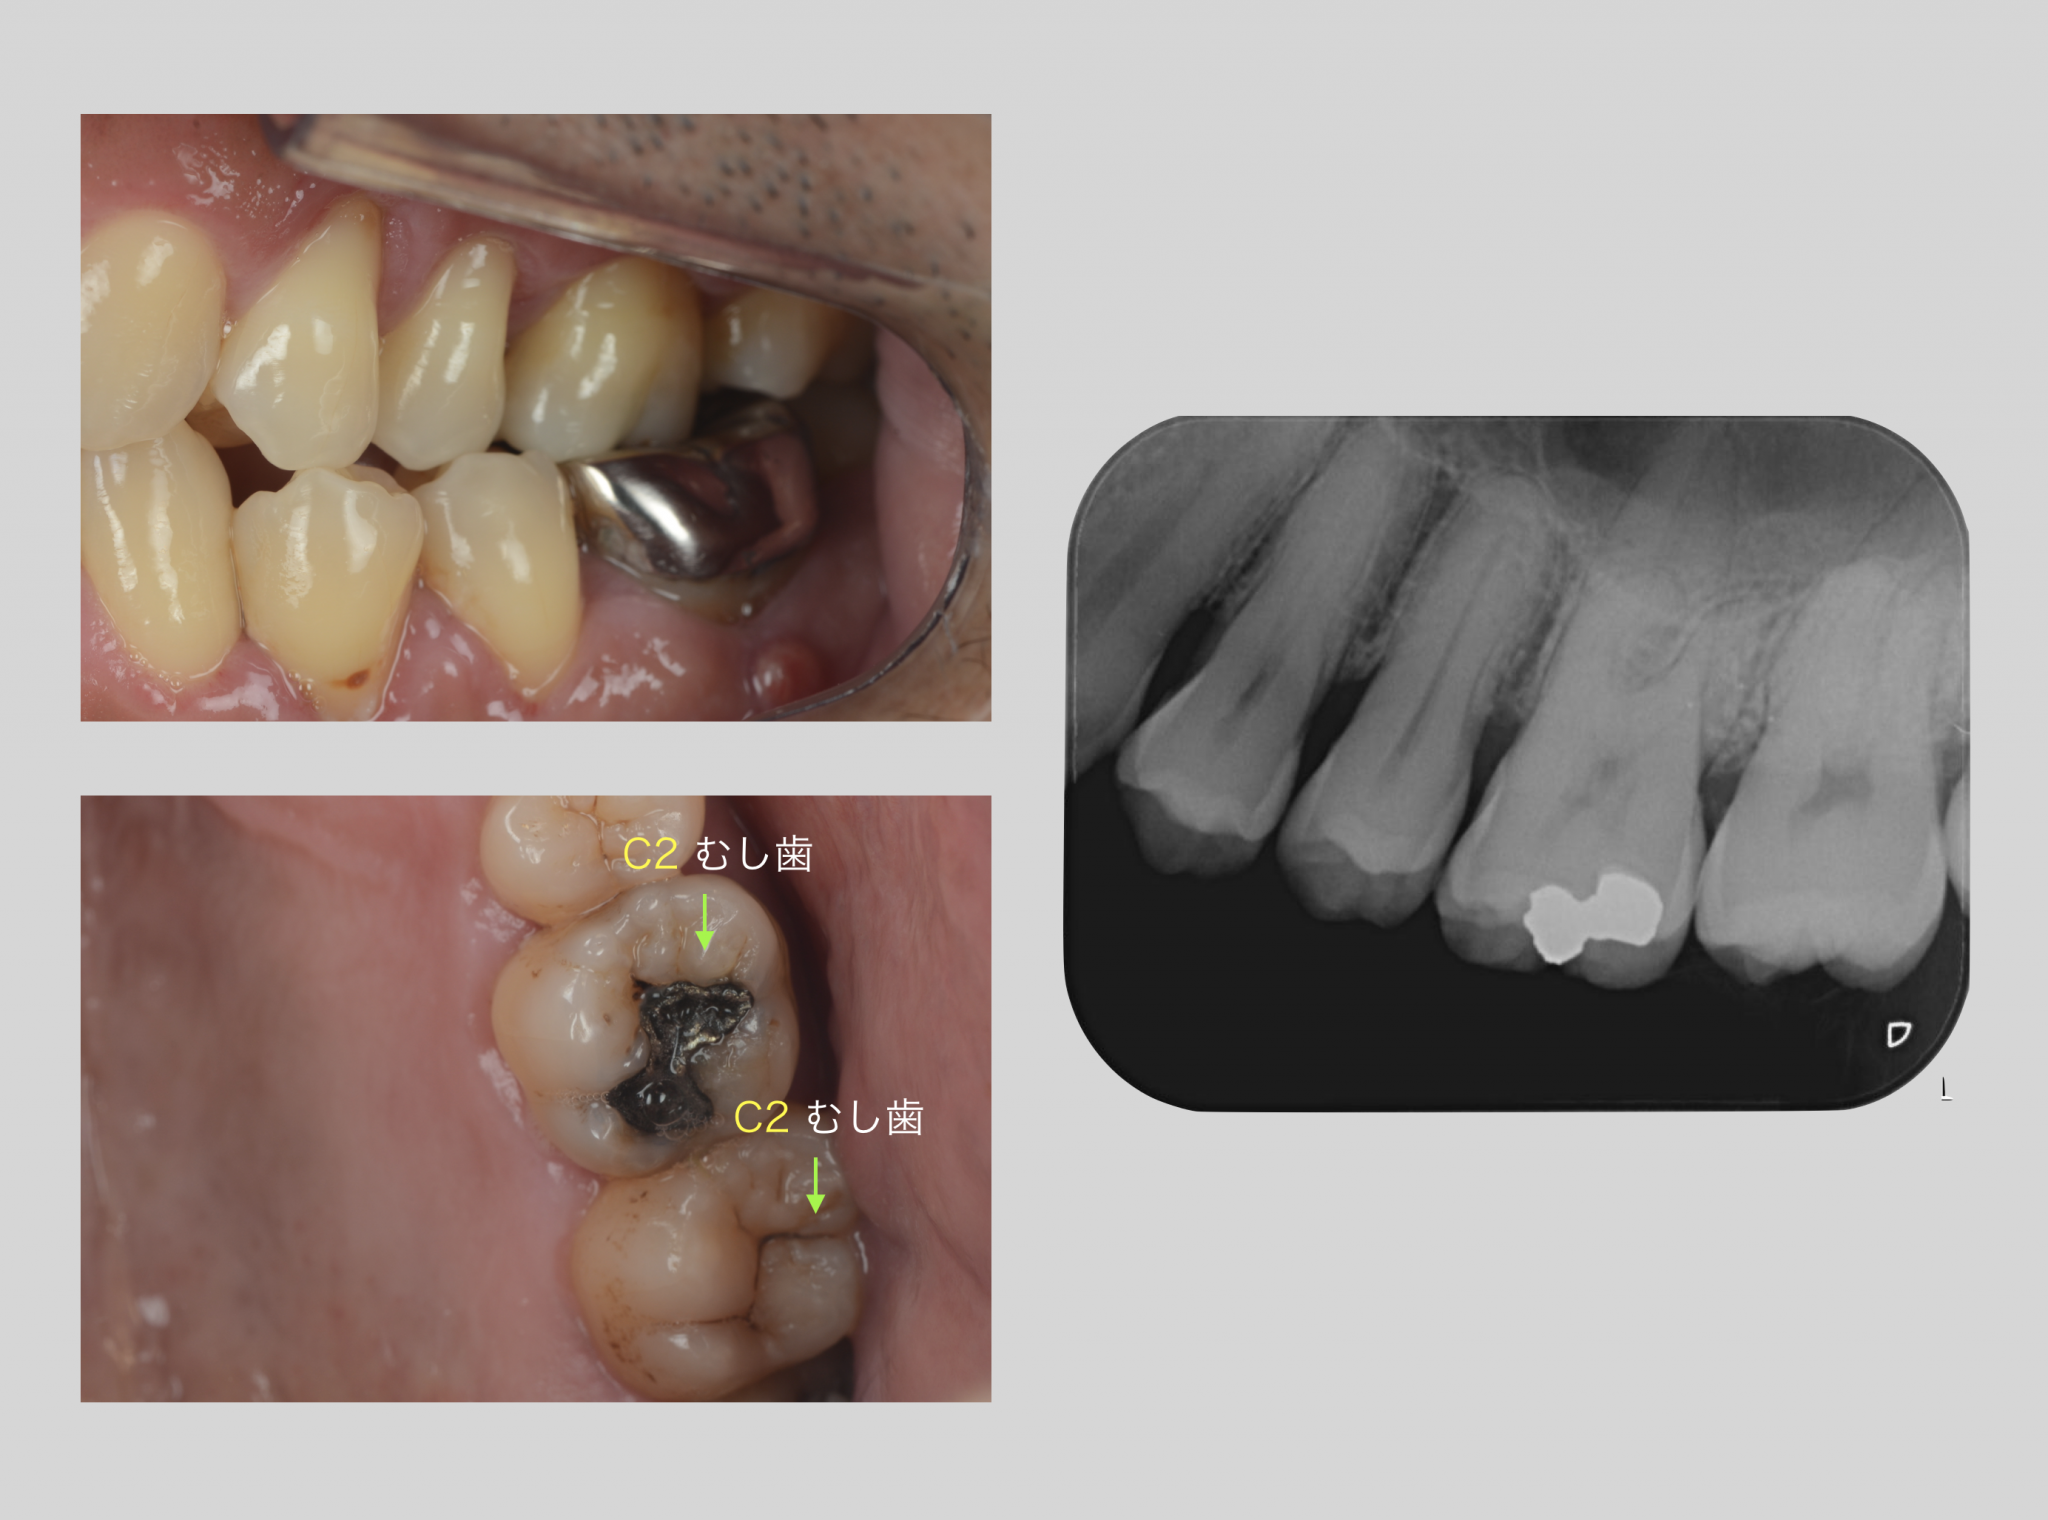

・レントゲン

・口腔内写真

検査結果はこのように ↑

こうすることによって、お口全体の情報が得られてより適切な処置が出来ますし、患者さんの生活スタイルに合わせて治療の予定が立てられるのです。